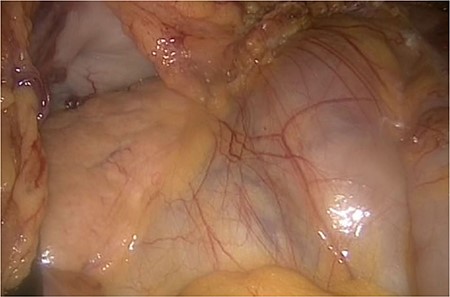

The laparoscopic anterior resection was performed in February 2019. The patient was positioned in a modified lithotomy position. The pneumoperitoneum was established by a Veress needle. The trocars were placed umbilical, two on the left and one on the right abdominal wall. The descending colon and the endoscopic ink-marked region were visualized perfectly. While getting an overview of the abdominal cavity, we noticed an abnormality in the ileum region. It seemed that the peritoneum was covering the entire ileum. The situs is depicted in Figs 1–4.

The entire small bowel was found retroperitoneal covered by a slim peritoneal layer (Fig. 1). The dorsal peritoneum covering the ileum was opened (Fig. 2).